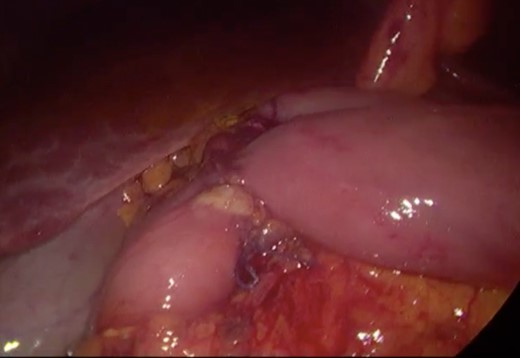

Initially, conservative management was adopted with some improvement of patient’s nutrition condition. However, as symptoms persisted, surgical treatment was recommended. Our surgical approach was a laparoscopic duodenojejunostomy with a latero-lateral stapled anastomosis between jejunum (30 cm from Treitz’s angle) and the second portion of the duodenum (Figs 5–9). The patient recovered with no pain but with a delay in diet acceptance. An upper GI contrast study was performed on the fifth post-operative day revealing a distended stomach with gastric emptying delay, but with unobstructed anastomosis, therefore without stenosis or leaks (Fig. 10). She was discharged home after 8 days with liquid diet and digestive transit restored. After 3 months of follow-up, the patient gained some weight and remained asymptomatic.

Surgery—laparoscopic visualization of the second and third portion of duodenum.